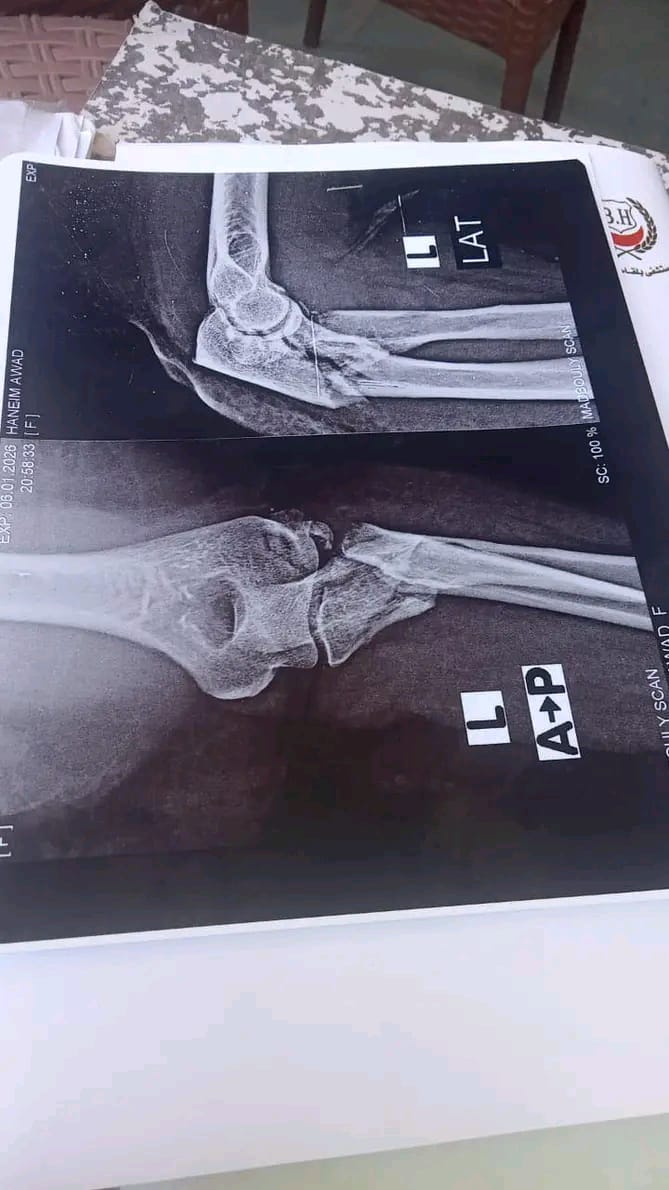

نجح الفريق الطبي بمستشفي بلقاس بمحافظة الدقهلية في إجراء جراحة تركيب مفصل صناعي وشريحة ومسامير لكسر مفتت بمفصل المرفق لمريضة تبلغ من العمر 55عامًا نتيجة سقوطها من ارتفاع.

قاد الجراحة الدكتور هشام خلاف، رئيس قسم العظام، بمشاركة الدكاترة هاني إسماعيل وكريم المشد، فيما أشرف على التخدير الدكتور حاتم صالح، استشاري التخدير ورئيس قسم العمليات، بمساندة الدكتور عصام عيد والدكتور عبد الرحمن الجوهرى، وفنية التخدير مس نورا عبدالفتاح.

كما شارك في تقديم الرعاية التمريضية كل من مس نصره زكريا ومس مني يوسف، تحت إشراف رئيسة التمريض مس سميرة مختار، وفني الأشعة كرم عبد الهادي، وقد وُضعت المريضة تحت الرعاية والملاحظة الدقيقة بالقسم بعد العملية.